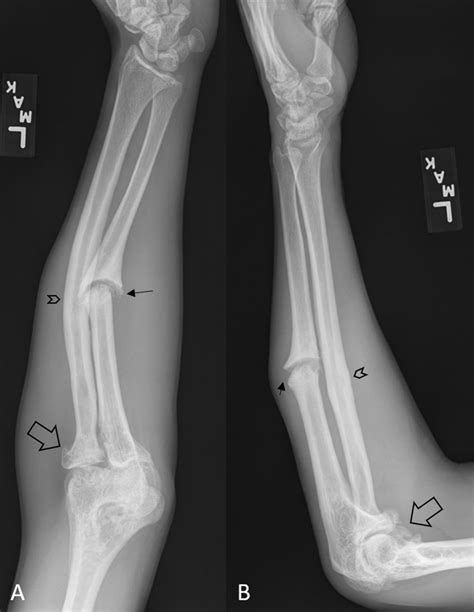

• Imaging Tests: X-rays are the primary diagnostic tool for identifying fractures. In some cases, additional imaging tests like CT scans or MRIs may be required for a more detailed view.

Imaging tests are crucial for determining the type and severity of the fracture, which will guide the treatment plan.

• Proximal Ulna Fracture: Occurs near the elbow joint.

• Midshaft Ulna Fracture: Occurs in the middle of the ulna.

• Comminuted Fracture: The bone shatters into multiple pieces.